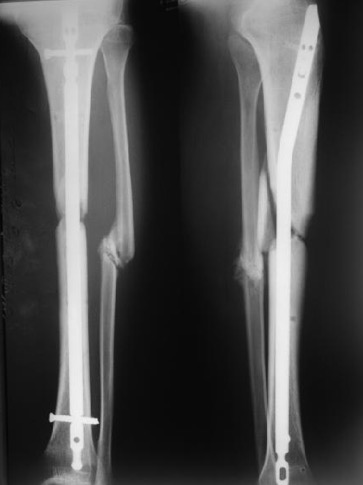

Совсем необязательно. Это при аппаратной фиксации, чтобы она не была бесконечной, надо обеспечить максимальную площадь контакта, или делать что-то дополнительное. Да и если фиксировать пластиной.

А когда в диафизе находится его эндопротез - достаточно сращения на ограниченном участке.

Это пример не про идентичный случай, а про категоричное утверждение, что "при интрамедуллярном остеосинтезе, конечно же, нужна...". Не нужна. Есть полный контакт - хорошо, нет - тоже не беда при интрамедуллярном остеосинтезе.

При аппаратном лечении - да, это проблема, когда срослось в виде песочных часов. И все время висит сакраментальный вопрос - уже можно снимать аппарат, или пусть еще походит?